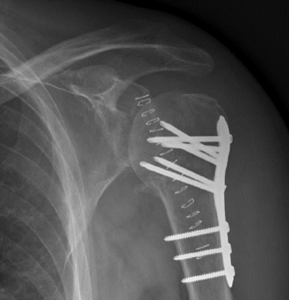

Latarjet ingreep

Deze open ingreep (met insnede van 8 tal centimeter vooraan op de schouder) wordt meestal uitgevoerd als er bijkomend een stukje bot is afgebroken van de kom of als de schouder opnieuw ontwricht na een vroeger uitgevoerde kijkoperatie. In sommige gevallen wordt dit als eerste keuze operatie uitgevoerd bv. atleten in contactsporten zoals rugby, mensen met een zwaar schouder belastend beroep.

Het voorste botuitsteeksel van het schouderblad (processus coracoïdeus) wordt losgemaakt en samen met de pezen erop getransplanteerd naar de voorzijde van de kom van de schouder (glenoid). Dit stukje bot wordt vastgezet met 2 schroeven. Het stukje bot zorgt voor een groter oppervlak van de kom, de pezen die erop vastzitten zorgen voor een bijkomende stevigheid zodat de schouder niet meer uit de kom kan.

Indien na vastgroeien van het stukje bot de schroeven hinder zouden geven kunnen die schroeven verwijderd worden.